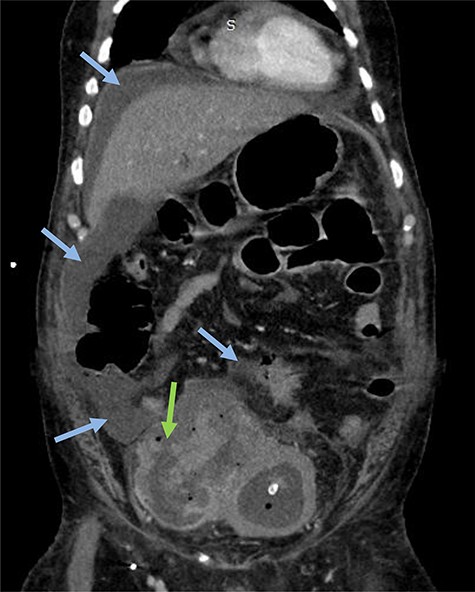

Emergency CT-scan showing intraperitoneal swallowing (blue arrows) due to a fistulization of the bladder (green arrow).

A 63-year-old man with a history of transurethral resection of prostate and a ballistic lithotripsy of bladder stone 15 years ago, presented with low urinary tract symptoms and hematuria. Cystoscopy showed multiple bladder stones and a bulky tumor mainly intradiverticular (Fig. 1). Partial resection of the tumor was done and pathology concluded on a squamous cell invasive bladder carcinoma. Since staging showed no metastatic lesion, a cystoprostatectomy was decided. Its execution was delayed because of a pulmonary embolism treated with curative anticoagulation and a severe paraneoplastic hypercalcemia treated with Zoledronic acid and veinous hydration on hospitalization. At Day 10 from admission and Day 60 after endoscopic resection of the tumor, the patient complained of abdominal pain, with diffuse tenderness and fever. Biology shows biologic inflammatory syndrome and kidney failure. Peritonitis was suspected and CT-scan showed a perforated bladder diverticulum with intraperitoneal effusion (Fig. 2). An emergency surgical investigation was executed, objecting a peritoneal cavity filled with nauseating hematic urine derived from a 2 cm disruption at the level of a posterolateral bladder diverticulum (Fig. 3). Radical cystectomy was performed. The patient was in severe septic shock requiring catecholamines and the procedure had to be shortened. No pelvic lymphadenectomy was done and bilateral ureterostomy was chosen as urinary diversion. The intervention lasted 2 h and there was no significant blood loss.